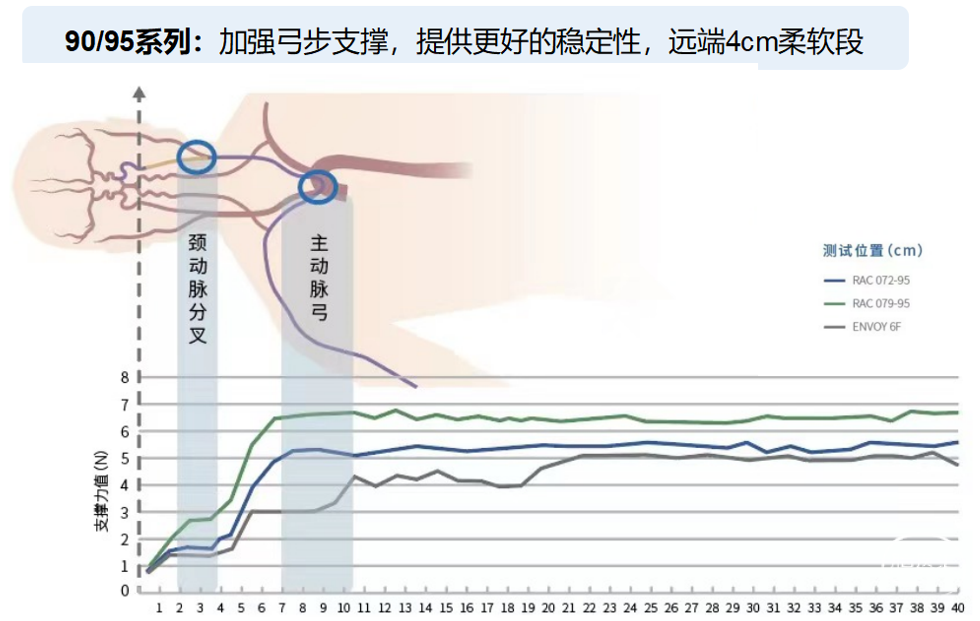

针对不同规格,更合理的分段设计: